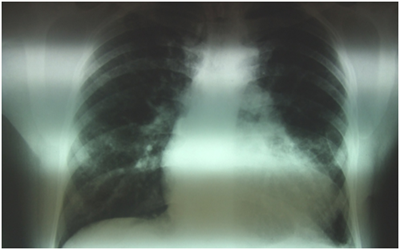

33 years old male patient, smoker, with a history of treated asthma , left posttraumatic pneumothorax with repeted pleurodesis, solved by surgery is admitted for dyspnea at rest, dry cough accentuated in clinostatism and cyanosis, symptoms that worsened two months before admission, onset two years ago. The clinical examination revealed a left latero-thoracic postsurgical scar, mixt cyanosis, rest dyspnea, dry cought, normal pulmonary auscultation, SpO2=97%, anterior chest pain, turgid jugular veins, tachycardia, BP=130/70mmHg, left parasternal continuous murmur of high intensity, accentuated by Valsalva maneuver, loud S 2 palpable in pulmonary area, systolic tricuspid murmur, no edemas, hepatomegaly and hepato-jugular reflux. Electrocardiogram (Figure 1) showed sinusal tachycardia, 120bpm, right bundle branch block, right axis deviation. The blood samples revealed myocardial and hepatic cytolyse, increased creatinine. On chest X-ray as showed in Figure 2 we found cardiomegalia, straight left middle cardiac arch, pulmonary stasis, latero-basal pachypleurites and left fissure inflamation. Performing the transthoracic ecocardiography (Figure 3a-3c) we noted normal LV systolic function, enlargement of the right cavities and pulmonary artery, mild mitral regurgitation, medium-mild pulmonary regurgitation, moderate functional tricuspidian regurgitation, noncoronary Valsalva sinus aneurysm ruptured into the RA with hemodynamic significant left to right shunt and mild pericardites. The contrast echocardiography found slow opacification of the right cavities without comunication between right and left cavities. During Valsalva maneuver on echocardiography air bubbles are visible into the right cavities with dissapearance after 10minutes of left lateral decubitus, during this event the patient`s dyspnea becomes more intense. The thoracic CT scan fails to find a broncho-vascular fistula. The transesophageal echocardiography better defines the communication without other congenital defects. Abdominal ultrasound reveales mild ascites and hepatosplenomegalia. He receives treatment with antialdosteronic and loop diuretic, unfractioned heparine, beta blockers , bronchodilator and intermitent oxygenoterapy. The patient is transferred for the surgical repair with good evolution and hemodynamic compensation. During surgery no other defects or fistulas were identified. On follow-up the patient was stable with mild pulmonary hypertension, one episode of atrial flutter and no signs of heart failure.1‒3

Figure 2 Thoracic asymetria due to scoliosis, cardiomegalia, pulmonary stasis, dilatation of pulmonary artery, pleural fibrosis.